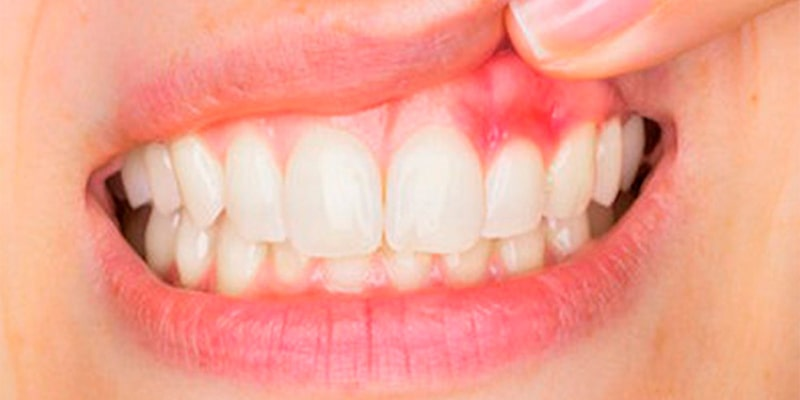

التهاب و تاول زدن لثه

التهاب و تاول زدن لثه، میتواند مرحله اول بیماری لثه باشد که منجر به عفونت لثه یا حتی بیماری مشکل آفرینتری به نام پیر دندانی شود. پیر دندانی، عفونت جدی لثه است که توسط باکتریهایی که روی دندانها و لثه، جمع شده اند، به وجود میآید. اگر پیر دندانی زود تشخیص داده شود و فرد بهداشت دهان و دندان را رعایت کند، این آسیب میتواند متوقف شود. این بیماری با ورم شروع شده و با گذر زمان، بدتر میشود.

التهاب معمولاً باعث قرمزی و ورم لثهها میشود. لثهها ممکن است به آسانی، خونریزی کنند؛ مانند وقتی که شخص، مسواک میزند. بعضیها ممکن است در ابتدا متوجه این مسئله نشوند. اگر چه نوع پیشرفته التهاب، منجر به عفونت در آن محل میشود و در این مرحله علائم ممکن است بیشتر ظهور پیدا کنند.